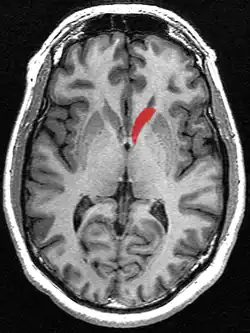

Transverse cut of brain (horizontal section), basal ganglia is blue | |

The caudate nuclei are near the center of the brain, sitting astride the thalamus. There is a caudate nucleus in each hemisphere of the brain. Each nucleus is C-shaped, with a wider "head" (caput in Latin) at the front, tapering to a "body" (corpus) and a "tail" (cauda). Sometimes a part of the caudate nucleus is called the "knee" (genu).[6] The caudate head receives its blood supply from the lenticulostriate artery; the tail of the caudate receives its blood supply from the anterior choroidal artery.[7]

The head and body of the caudate nucleus form part of the floor of the anterior horn of the lateral ventricle. The body travels briefly towards the back of the head; the tail then curves back toward the anterior, forming the roof of the inferior horn of the lateral ventricle. This means that a coronal section (on a plane parallel to the face) that cuts through the tail will also cross the body and head of the caudate nucleus.